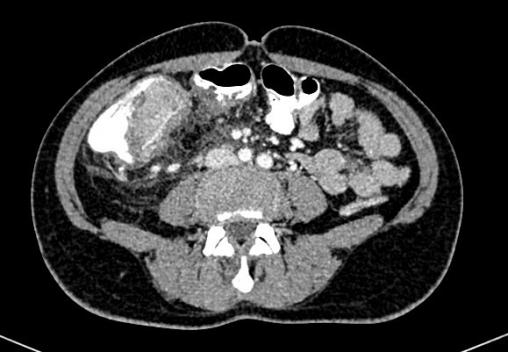

Matthieu Roulleaux Dugage, La Revue du Praticien Syndrome occlusif avec masse colique gauche et perforation contenue dans le mésocolon.